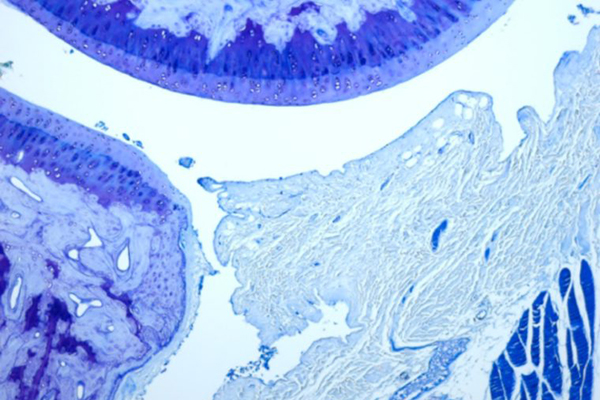

Lake and his collaborators at the School of Medicine — Aaron Chamberlain, MD, assistant professor of orthopedic surgery, and Ken Schechtman, associate professor of biostatistics — are using an animal model to study elbow joint contracture and identify which soft tissues contribute to range of motion loss. The research team will build upon previous work by evaluating how medications and physical therapy can improve recovery.